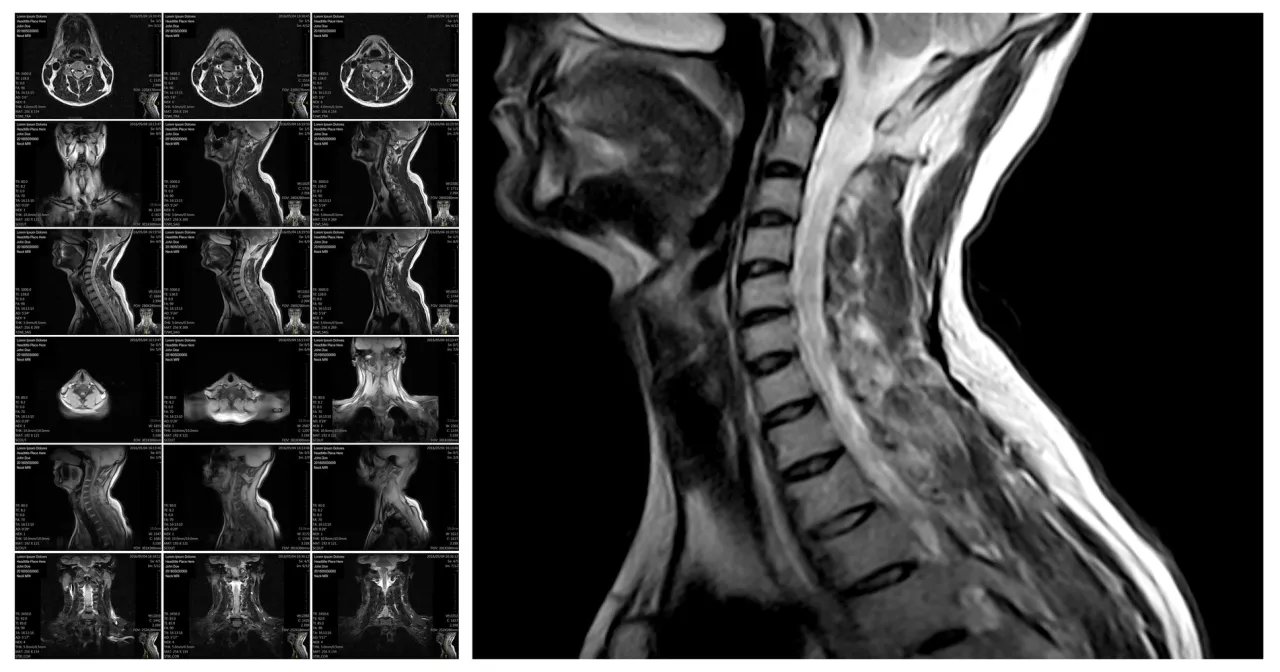

Skierowanie na rezonans magnetyczny kręgosłupa jest kluczowym krokiem w procesie diagnostycznym, który umożliwia lekarzom dokładne zbadanie stanu kręgosłupa pacjenta. W Polsce, skierowanie to może wystawić lekarz specjalista, który posiada odpowiednią wiedzę i doświadczenie w diagnozowaniu schorzeń kręgosłupa. W niektórych przypadkach, lekarz podstawowej opieki zdrowotnej (POZ) również może wystawić takie skierowanie, ale tylko w określonych okolicznościach zdrowotnych.

Istnieje wiele objawów i stanów zdrowotnych, które mogą prowadzić do wystawienia skierowania na rezonans magnetyczny kręgosłupa. W przypadku pacjentów z przewlekłym bólem kręgosłupa, który nie ustępuje pomimo leczenia, lekarze często zalecają wykonanie MRI, aby zidentyfikować ewentualne zmiany strukturalne. Inne sytuacje, takie jak podejrzenie zmian zwyrodnieniowych czy objawy neurologiczne, również mogą być podstawą do skierowania na to badanie. Zrozumienie tych symptomów jest kluczowe dla szybkiej i skutecznej diagnostyki.Objawy, które mogą prowadzić do skierowania na MRI

Wiele objawów może wskazywać na potrzebę wykonania rezonansu magnetycznego. Przewlekły ból pleców, który nie reaguje na standardowe leczenie, może sugerować poważniejsze problemy, takie jak dyskopatia czy ucisk na nerwy. Neurologiczne objawy, takie jak drętwienie, mrowienie, czy osłabienie kończyn, również powinny skłonić pacjenta do konsultacji z lekarzem. Warto zwrócić uwagę na inne symptomy, takie jak ograniczenie ruchomości kręgosłupa czy ból promieniujący do nóg, które mogą również wymagać dalszej diagnostyki.